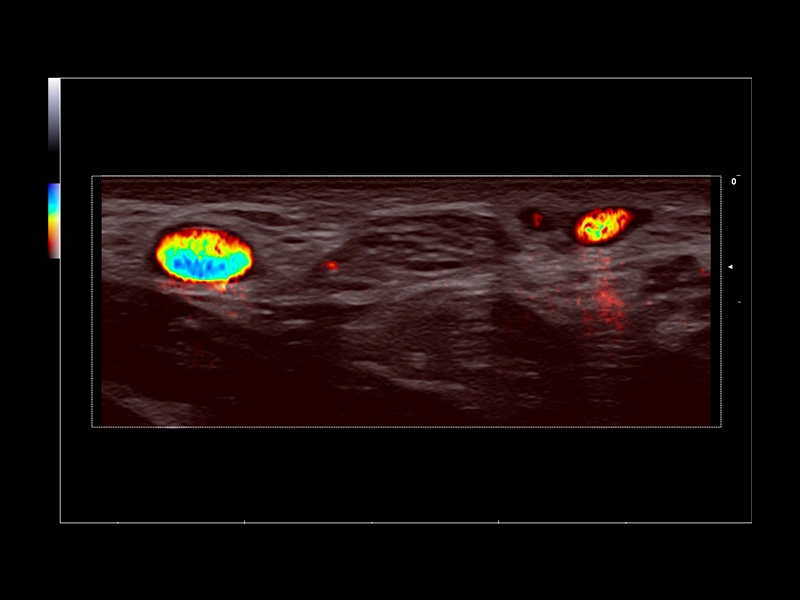

MyLab™9 Platform - XFlow in testis vascularization

MyLab™9 Platform - XFlow in testis vascularization